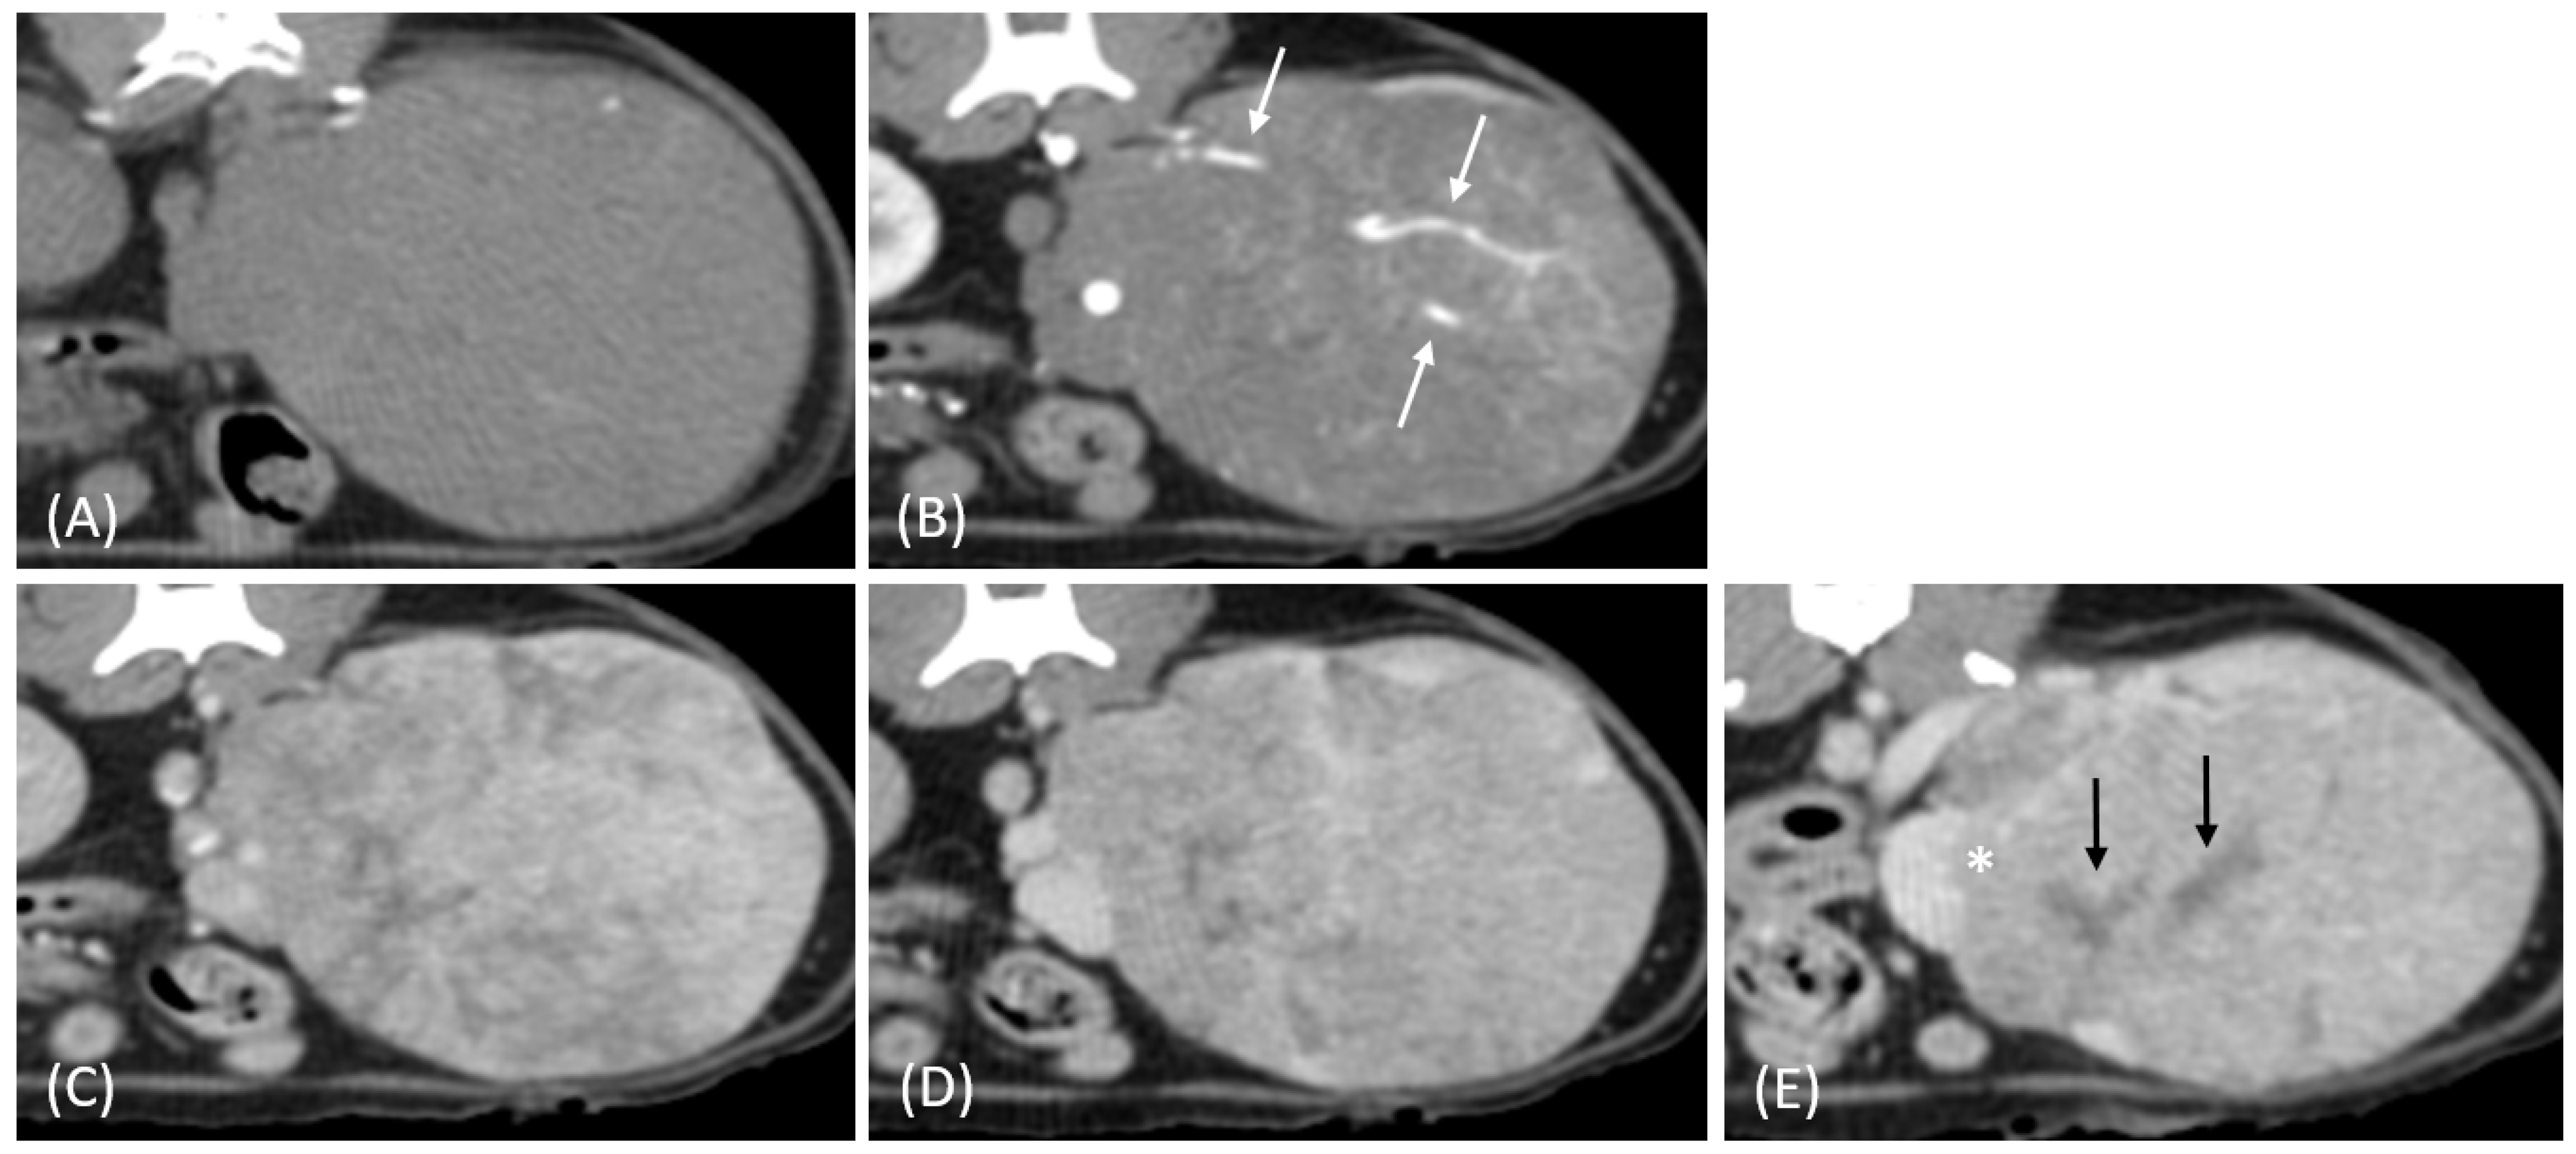

Figure 7.

(A) Pre-contrast and (B) late nephrographic/early excretory phase contrast-enhanced computed tomography (CT) images of a renal cell carcinoma (RCC). The image shows a large renal mass with rim enhancement and no internal enhancement. Vascular structures such as the aorta (white arrow) and CVC (black arrow) are visible; however, the renal artery and vein are not clearly identifiable. Tumor invasion into adjacent musculature is observed (arrowhead).

In the two cats that were excluded, the RCC tumors showed a distinct imaging pattern with rim enhancement but no internal enhancement on contrast-enhanced CT (Figure 7). The attenuation values of the tumors were approximately 23 HU and 33 HU across both the pre- and post-contrast phases.

Two RCC cases in this study exhibited a distinct imaging pattern characterized by rim enhancement without internal enhancement. This imaging feature likely reflects central necrosis or hypovascularity resulting from rapid tumor growth outpacing its blood supply. Additionally, one of the two cases demonstrated invasion into adjacent musculature, further supporting the aggressive nature of these tumors. While necrosis is a common cause of non-enhancement in tumors, other factors such as cystic changes, fibrosis, or hemorrhage may also contribute to this imaging feature [35]. Both cats succumbed to their disease within one month of diagnosis, suggesting the poor prognosis associated with this imaging pattern. Although histopathological confirmation was unavailable, these findings suggest the diagnostic value of imaging in characterizing aggressive tumors.